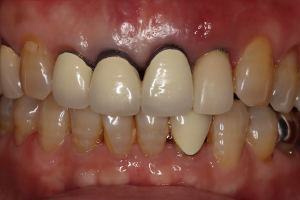

症例

オールセラミック(e-max)

治療前

治療後

治療前のレントゲン

治療後のレントゲン

歯肉退縮により、以前他院で製作されたセラミック冠の審美障害があります。また時々、根元が腫れていたとのこと。前歯4本すべて根管治療を行い、ファイバーコアを入れてからオールセラミック(e-max)で修復しました。術後のレントゲンでは根尖性歯周炎が改善しています。

5ヵ月・20回

¥600,000